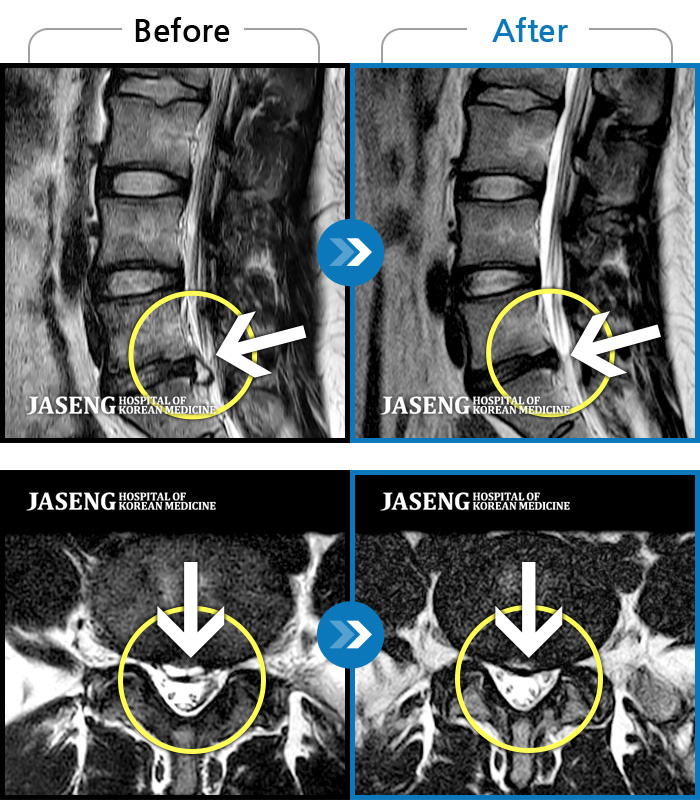

MRI ũ ʸ Ȯϼ.

ȯںп Ǹ ǿ ԿǾ, ο ġ ۿ Ƿ ġḦ Ͻñ ٶϴ.